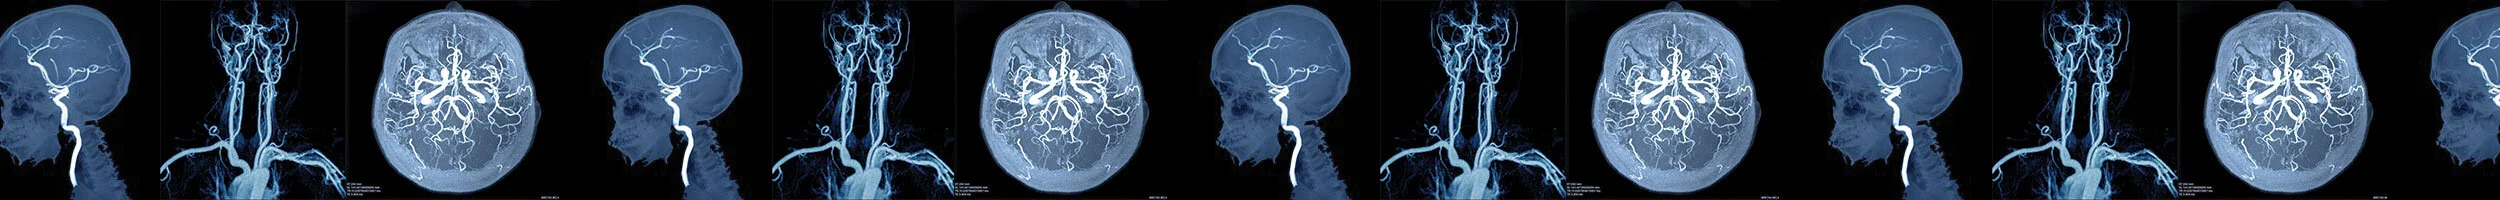

We receive patients from anywhere in Ontario. If your patient needs extraordinary care at a cutting edge facility with the nation’s top practitioners, consider referring them to the St. Michael’s Neurovascular Centre. Examples of conditions we treat: